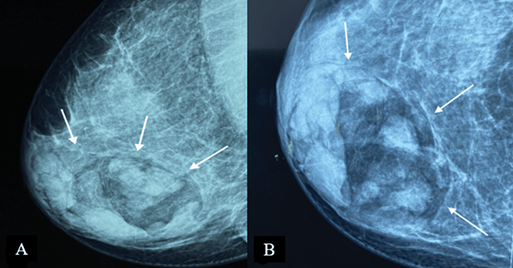

Mammography

On mammography, MH is typically seen as an inhomogeneous oval or round formation, with radio-opaque and radiotransparent areas that reflect the presence of tissues of different densities (Figure 2). The lesion bears a thin, well-defined radiopaque border (pseudocapsule). The presence of different densities within the pseudocapsule tends to create a pathognomonic impression of a “slice of salami” [2, 25] or a bull’s eye [2] or a “breast within a breast” [26].

Figure 2. Digital mammography: medio-lateral oblique (A) and cranio-caudal (B) projections of the right breast – a large, well-defined mass containing radiolucent (fat) and radiopaque (soft tissue) densities can be seen. It is surrounded by a thin radiopaque capsule, presenting a “breast within a breast” appearance. Image credits: El Yousfi Z, El Mansoury FZ, El Bakkari A, Omor Y, Latib R. Breast hamartoma with synchronous contralateral breast cancer: a case report. Cureus 2024; 16(8): e66534. DOI: 10.7759/cureus.66534. Reused under the terms of the Creative Commons Attribution License CC-BY 4.0. (https://creativecommons.org/licenses/by/4.0/deed.en).